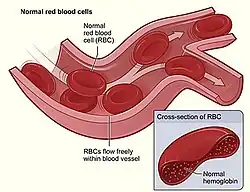

Anemia (also spelt anaemia in British English) is a blood disorder in which the blood has a reduced ability to carry oxygen. This can be due to a lower than normal number of red blood cells, a reduction in the amount of hemoglobin available for oxygen transport, or abnormalities in hemoglobin that impair its function.[3][4] The name is derived from Ancient Greek ἀν- (an-) 'not' and αἷμα (haima) 'blood'.[5]

It is difficult to directly measure RBC mass,[66] so the hematocrit (amount of RBCs) or the hemoglobin (Hb) in the blood are often used instead to indirectly estimate the value.[67] Hematocrit; however, is concentration-dependent and is therefore not completely accurate. For example, during pregnancy, a woman's RBC mass is normal, but because of an increase in blood volume, the hemoglobin and hematocrit are diluted and thus decreased. Another example would be bleeding, where the RBC mass would decrease, but the concentrations of hemoglobin and hematocrit initially remain normal until fluids shift from other areas of the body to the intravascular space.

Anemia is typically diagnosed on a complete blood count. Apart from reporting the number of red blood cells and the hemoglobin level, the automatic counters also measure the size of the red blood cells by flow cytometry, which is an important tool in distinguishing between the causes of anemia. Examination of a stained blood smear using a microscope can also be helpful, and it is sometimes a necessity in regions of the world where automated analysis is less accessible.